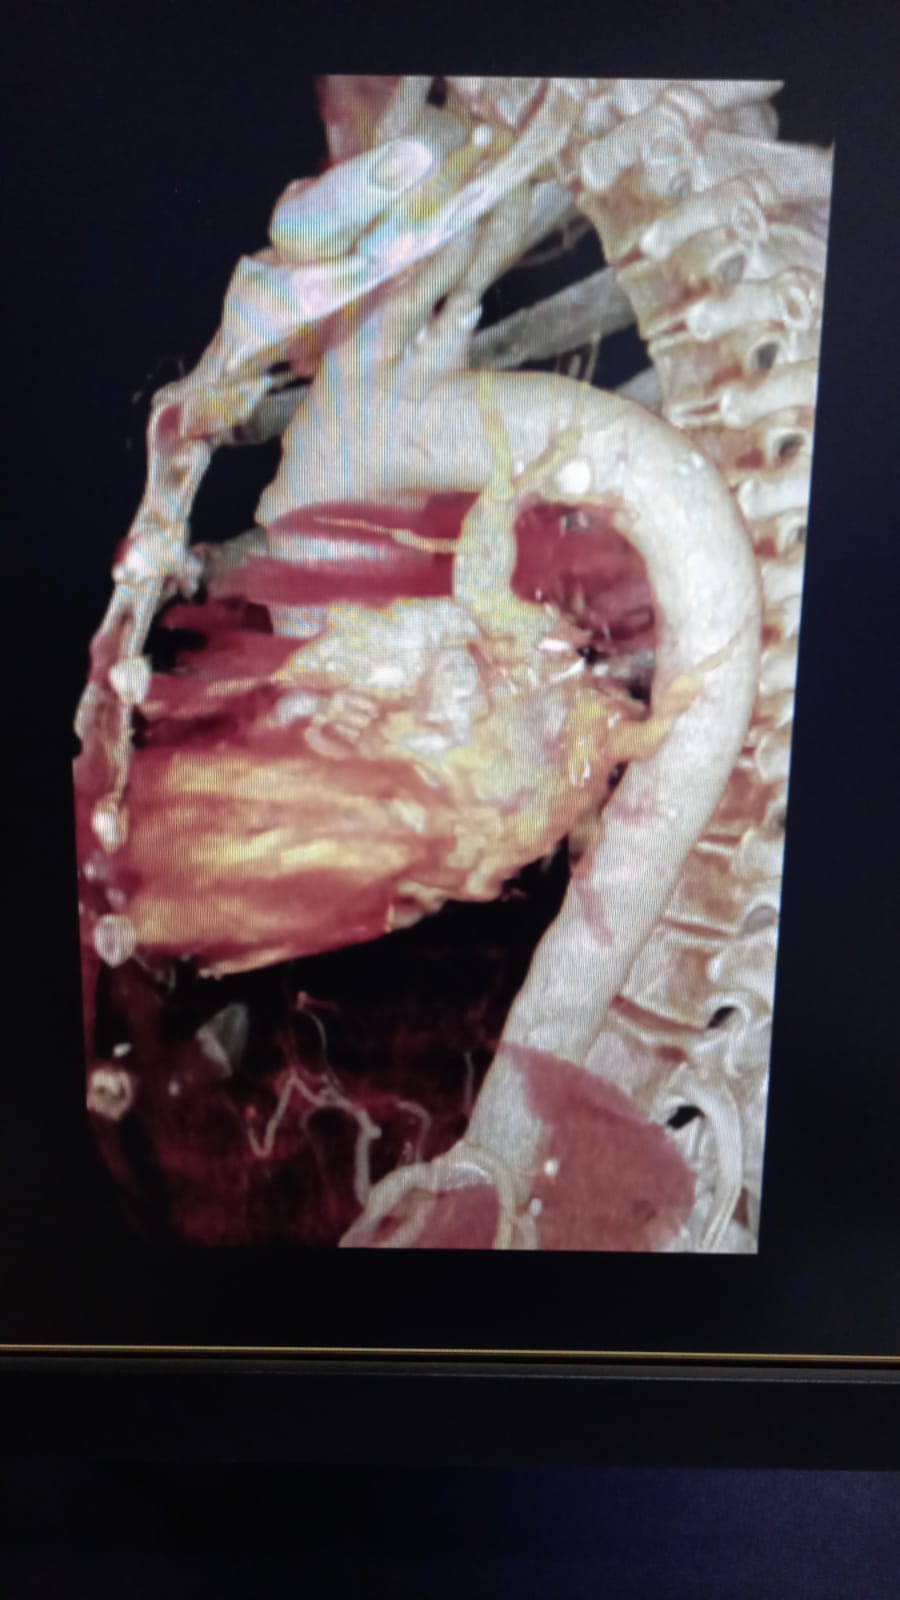

La reconstrucción virtual es una técnica avanzada en radiología diagnóstica que aprovecha la tecnología de tomografía computarizada (TC) para crear representaciones detalladas y precisas del cuerpo humano en tres dimensiones. Este proceso transforma las imágenes obtenidas por el escáner TC en modelos tridimensionales que reflejan fielmente la anatomía y estructuras internas del paciente.

La reconstrucción virtual se realiza utilizando equipos de tomografía computarizada especializados. Durante el procedimiento de TC, el paciente se coloca en una camilla que se desliza hacia el escáner, el cual captura múltiples imágenes transversales del área de interés. Estas imágenes son luego procesadas por potentes computadoras que utilizan algoritmos avanzados para reconstruir una imagen tridimensional completa.

- Diagnóstico Preciso: La reconstrucción virtual permite a los médicos visualizar con precisión estructuras anatómicas complejas, detectar anomalías, evaluar la extensión de lesiones o enfermedades, y realizar diagnósticos más precisos.

- Planificación Terapéutica: Al proporcionar una representación detallada y realista del área afectada, los médicos pueden planificar estrategias terapéuticas más efectivas y personalizadas. Esto es especialmente útil en cirugías complejas donde la precisión es crucial.

En resumen, la reconstrucción virtual mediante tomografía computarizada representa un avance significativo en la precisión diagnóstica y la planificación terapéutica en medicina. Esta tecnología no solo mejora la capacidad de los médicos para identificar y tratar diversas condiciones médicas, sino que también optimiza los resultados clínicos al proporcionar una visión detallada y completa del cuerpo humano en tres dimensiones. Para obtener más información sobre cómo la reconstrucción virtual puede beneficiarte, consulta con un especialista en radiología o medicina diagnóstica para explorar las opciones disponibles según tus necesidades médicas específicas.